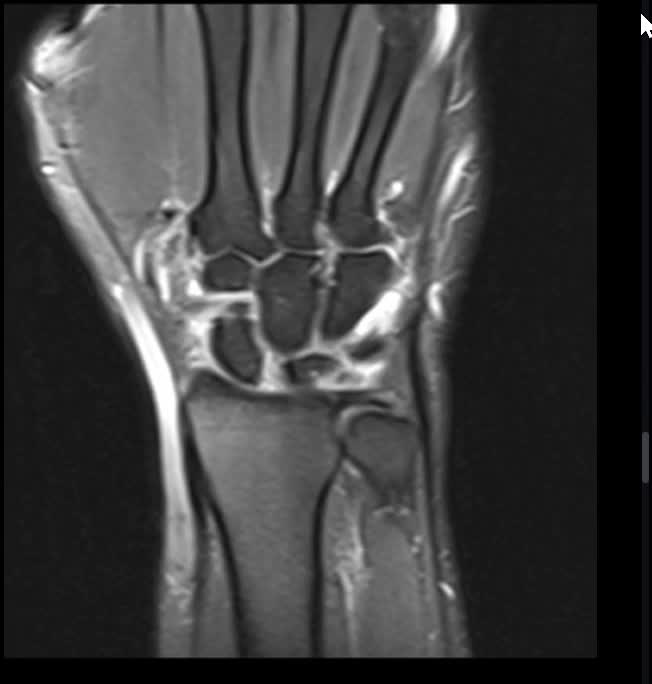

A 28-year-old male reports to the orthopedic clinic with a 6-week history of left wrist pain. One and a half months prior, he crashed on his bike and caught himself with his hands. Injury and repeat films report no acute osseous abnormality. He endorses weakness and pain when gripping heavy objects. He is tender over the anatomic snuff box on physical exam. He also experiences pain when his wrist deviates from ulnar to radial with force applied to the scaphoid tubercle. A video of his wrist MRI is seen in Figure A. If his injury is not addressed, what carpal deformity will initially develop?